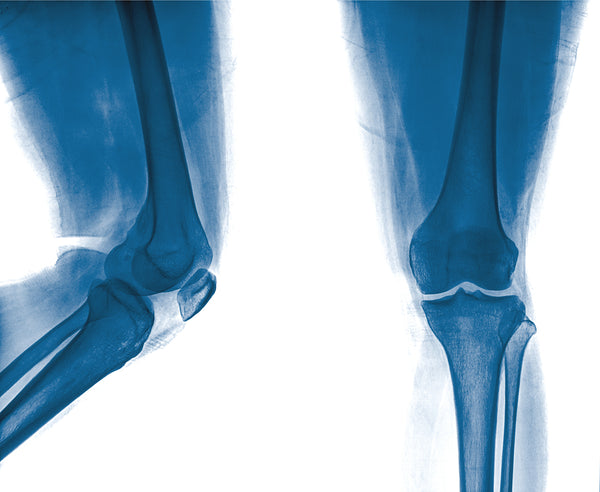

The connection between foot mechanics and knee pain

Structural issues like high or low arches and wider or narrower feet can cause misalignments and mechanical problems that put increased stress on the muscles in the calves and shins. This in turn can negatively affect the way the knee rotates and can potentially lead to knee pain due to increased wear and tear from activities including:

Knee pain can be a very complicated condition with a wide variety of causes and treatment options. It’s important to meet with a qualified medical professional for any knee pain that lasts longer than a few days to a week. In addition to other treatment options, foot orthotics are a common recommendation, especially if a physical examination reveals a misalignment in the feet.